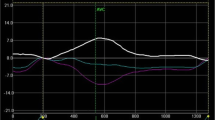

Comparisons of echocardiography parameters between HCM and control groups are presented in Table 2. Among 122 patients, the mean Bas-Rotation was 7.4°, mean AP-Rotation was 9.9°, mean LV-Twist was 17.3°, mean LVEF was 69.2 %, mean LADs was 37.4 mm, mean LVDd was 42.3 mm, mean IVST was 16.3 mm, mean LAVi was 43.5 ml/m2, mean E/A was 1.1, mean E/Em was 12.3 and mean LVMI was 100.2 g/m2. The HCM group had significantly higher values for Bas-Rotation, AP-Rotation, LV-Twist, LVEF, LADs, LAVi, IVST, LVPWT, RWT, E/Em and LVMI than the control group (all p < 0.0001). LVDd and E/A were significantly lower in the HCM group than in the control group (both p < 0.001) (Table 2). Representative examples are shown in Fig. 1.

The distribution of characteristics in HCM patients with and without fibrosis is presented in Table 3. In the 76 HCM patients, means for Bas-Rotation, AP-Rotation, LV-Twist, LADs, LAVi, IVST, LVPWT, RWT, E/Em, and LVMI were all significantly higher in the fibrosis group than in the non-fibrosis group (p < 0.001). Means of age and E/A were significantly lower in the fibrosis group compared with non-fibrosis group (age: 44.6 vs. 51.7 years, p = 0.007; E/A: 1.0 vs. 1.2, p = 0.001). No significant differences were found between non-fibrosis vs. fibrosis groups in heart rate, BSA, BMI, SBP, DBP and LVEF (p > 0.05). Representative examples are shown in Fig. 2.